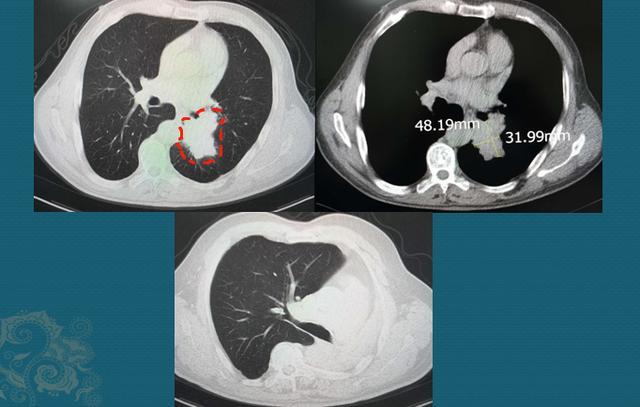

这是一位64岁男病人,老烟民,牙齿都是焦黄的,反复咳嗽、痰多40天,胸闷10天,CT发现左侧中心型肺癌:

图片

下面的图是手术后3.5年复查,左肺全切,没有复发

中心型肺癌手术要慎重,需要术前充分评估,除了排查有无远处转移之外,还要重点观察对肺门血管、气管的侵袭范围,判断有无手术条件。

随着胸外科各种微创技术的进步,很多禁区也在不断突破!豪大夫最佩服的就是胸外科医生,因为肺癌发病率最高,而每一个小突破都能给成千上万的病带来新希望!这位病人做了左侧全肺切除,昨天回来复查,已经3年半了,没有复发。